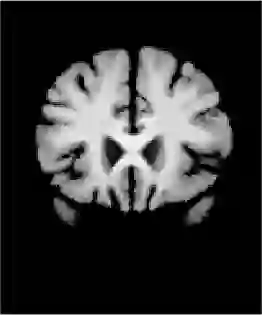

Unsupervised image registration commonly adopts U-Net style networks to predict dense displacement fields in the full-resolution spatial domain. For high-resolution volumetric image data, this process is however resource-intensive and time-consuming. To tackle this problem, we propose the Fourier-Net, replacing the expansive path in a U-Net style network with a parameter-free model-driven decoder. Specifically, instead of our Fourier-Net learning to output a full-resolution displacement field in the spatial domain, we learn its low-dimensional representation in a band-limited Fourier domain. This representation is then decoded by our devised model-driven decoder (consisting of a zero padding layer and an inverse discrete Fourier transform layer) to the dense, full-resolution displacement field in the spatial domain. These changes allow our unsupervised Fourier-Net to contain fewer parameters and computational operations, resulting in faster inference speeds. Fourier-Net is then evaluated on two public 3D brain datasets against various state-of-the-art approaches. For example, when compared to a recent transformer-based method, named TransMorph, our Fourier-Net, which only uses 2.2\% of its parameters and 6.66\% of the multiply-add operations, achieves a 0.5\% higher Dice score and an 11.48 times faster inference speed. Code is available at \url{https://github.com/xi-jia/Fourier-Net}.